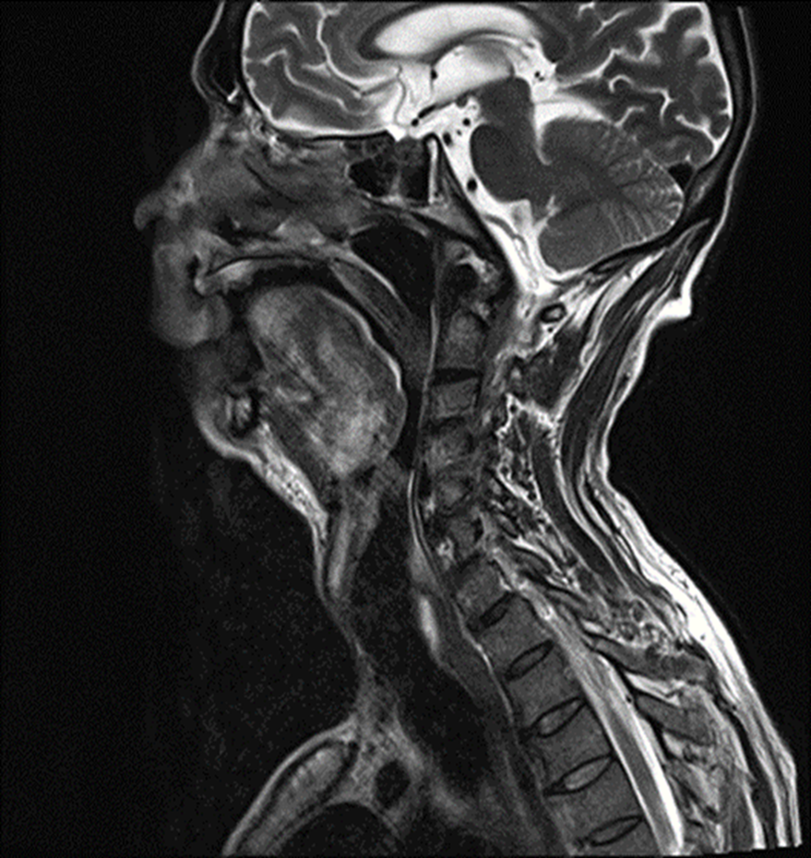

Clinical Repercussions of Guillain-Barré Syndrome: A Case Study and Systematic Review

Lígia Maria Oliveira de Souza, Paloma Marcela Vigilato , Alessandra Savi Bellizzi, Dalle Jayder Braga Alencar, Gustavo Mendes Rezende Costa, Andrea Paola Britos Gomez, Bárbara Priscila Alves de Souza, José Andrés Alfonzo Segovia

Open-Lip Schizencephaly in Adulthood

Joana Freitas Ribeiro, Cátia Gorgulho, Ana Matos

Colloid Cyst of the Third Ventricle – A Rare Cause of Headache

Joana Freitas Ribeiro, Cátia Gorgulho, Ana Matos, Tiago Alves